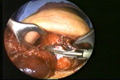

العمليات الجراحية التصويرية بالفيديو المنظاري

Videoendoskopik (Kapalı) Cerrahi

Ameliyat'tan Görüntüler